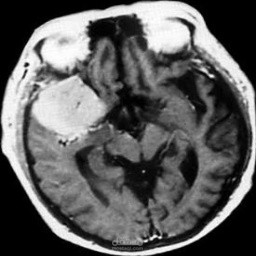

This project focuses on building a machine learning model to classify brain MRI scans as either healthy or affected by a tumor. The dataset contains MRI images of brains labeled as normal or tumor. The images are preprocessed by resizing and normalizing them, then augmented to improve model generalization. The dataset is split into training and testing sets, and a Convolutional Neural Network (CNN) is trained to learn patterns and features associated with healthy and abnormal brains. Finally, the model can predict the condition of the brain when a new MRI scan is provided.